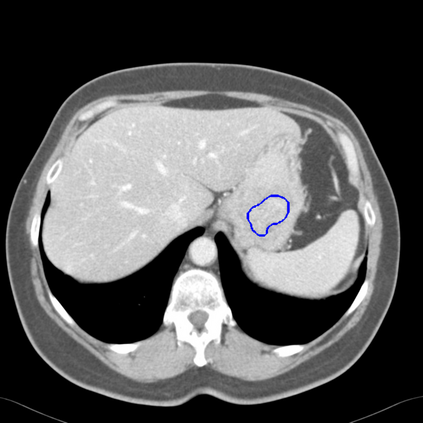

Radiomics uses quantitative medical imaging features to predict clinical outcomes. Currently, in a new clinical application, finding the optimal radiomics method out of the wide range of available options has to be done manually through a heuristic trial-and-error process. In this study we propose a framework for automatically optimizing the construction of radiomics workflows per application. To this end, we formulate radiomics as a modular workflow and include a large collection of common algorithms for each component. To optimize the workflow per application, we employ automated machine learning using a random search and ensembling. We evaluate our method in twelve different clinical applications, resulting in the following area under the curves: 1) liposarcoma (0.83); 2) desmoid-type fibromatosis (0.82); 3) primary liver tumors (0.80); 4) gastrointestinal stromal tumors (0.77); 5) colorectal liver metastases (0.61); 6) melanoma metastases (0.45); 7) hepatocellular carcinoma (0.75); 8) mesenteric fibrosis (0.80); 9) prostate cancer (0.72); 10) glioma (0.71); 11) Alzheimer's disease (0.87); and 12) head and neck cancer (0.84). We show that our framework has a competitive performance compared human experts, outperforms a radiomics baseline, and performs similar or superior to Bayesian optimization and more advanced ensemble approaches. Concluding, our method fully automatically optimizes the construction of radiomics workflows, thereby streamlining the search for radiomics biomarkers in new applications. To facilitate reproducibility and future research, we publicly release six datasets, the software implementation of our framework, and the code to reproduce this study.